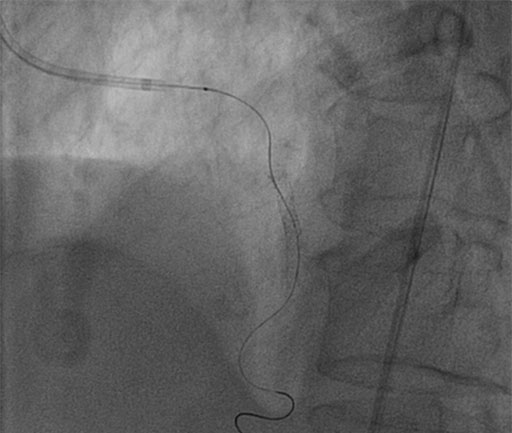

IVUS Guided RCA Assessment

• IVUS reveals MLA of 3.2mm2

• COMET™ wire re-connected

• FFR of 0.88, PCI not necessary of RCA

non significant FFR 0.88